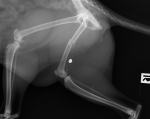

(Pies postrzelony w Łące Prudnickiej)

Jak informuje Komenda Powiatowa Policji w Prudniku - do zdarzenia doszło 12 kwietnia przed godziną 7:00 w miejscowości Łąka Prudnicka na ulicy Chocimskiej lub w jej okolicy. Jak ustalili pracujący na miejscu policjanci, pies uciekł z posesji gdy jego właściciel wyszedł do sklepu. W trakcie swojej wyprawy został postrzelony z wiatrówki z bliskiej odległości.

Całę szczęście pies trafił szybko pod opiekę weterynarza i wyszedł cało z tej bestialskiej zabawy, nie zagraża mu już niebezpieczeństwo.